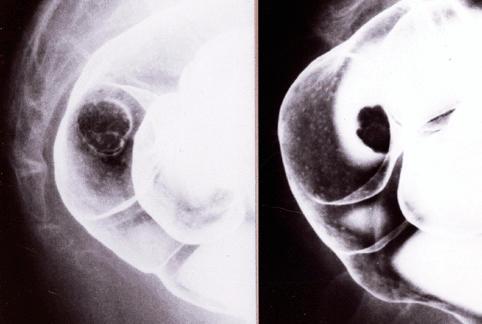

疾病(病理主体)的分类恶性上皮性肿瘤/腺癌

部位(按器官分)大肠/直肠

检查方法X线

肿瘤的肉眼分类0型(表在型)/I型(Is)

肿瘤最大直径15~19

肿瘤的深度sm